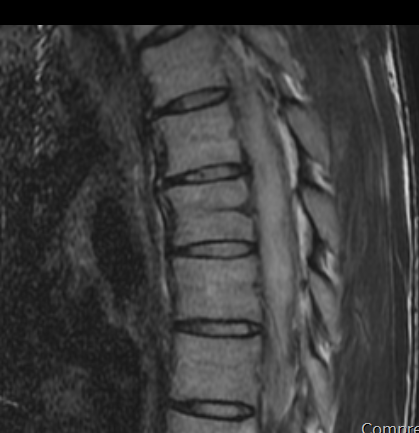

척추 mri를 찍어서 봤는데 저런식으로 홈이나 금간것저럼 보이는게 있는데 저건 뭔가요???

뼈에 금이 간게 아니라면 뭔지 궁금합니다

• 2번 째 사진

이런 경우에 골절이 아닌지 오해하시는 경우가 많은데 골절이 아닙니다.

골절의 경우에는 T1 영상에서 조영이 떨어지고 fat suppression T2 영상에서 조영이 증가하는 소견을 확인해야합니다.

골절이 아니면 왜 저렇게 보이는지 까지는 제가 잘 모르지만 저 소견을 이상소견으로 보이는 않습니다.